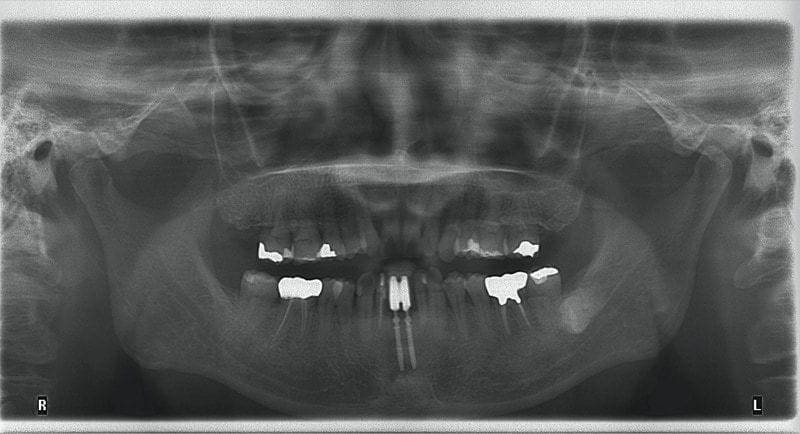

Mr.Hsieh是我治療的牙周病患者。他曾在其他地方接受下顎正中門齒人工植牙療程。但假牙裝上後,時常容易塞到食物殘渣。不容易清潔維護的情況下,植牙的周圍牙齦不只一次腫脹發炎。我幫他檢查過後,診斷為全口中度牙周病。

因此建議全口牙周治療,並且改善口腔衛教。牙齦狀況在一兩個月內就獲得改善。並且他非常配合定期追蹤回診,十年過去了都不曾間斷。因此多年來全口牙周狀況都能維持穩定,沒有增加缺牙的數目。

圖示:Mr.Hsieh術前環口全景X光片